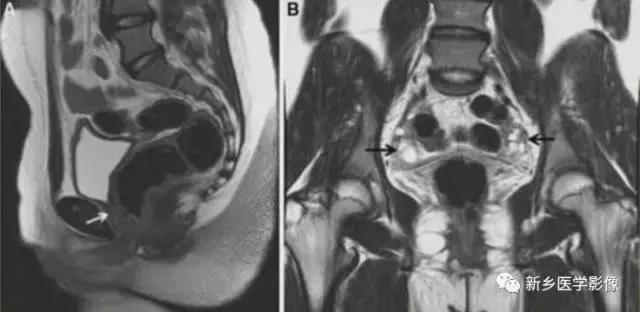

III:双子宫

双子宫:子宫和宫颈完全不融合,两宫角完全分离,宫颈两个,阴道75%

伴分隔。

上图:双子宫:双侧子宫及宫颈完全分离

双子宫:双侧子宫完全分离,右侧阴道积血(阴道斜隔),宫腔积血,呈长T2信号。

右侧先天性肾缺如。